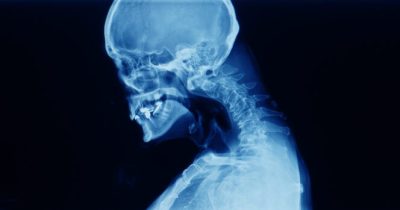

23-jarige ontwikkelt zeldzame aandoening genaamd ‘gevallen hoofd syndroom’

Verslaving kan verschillende problemen veroorzaken bij mensen die eraan lijden. De impact van verslaving op je lichaam hangt van veel factoren af, voornamelijk van de stof die je gebruikt. Deze 23-jarige man ontwikkelde een zeldzame ...